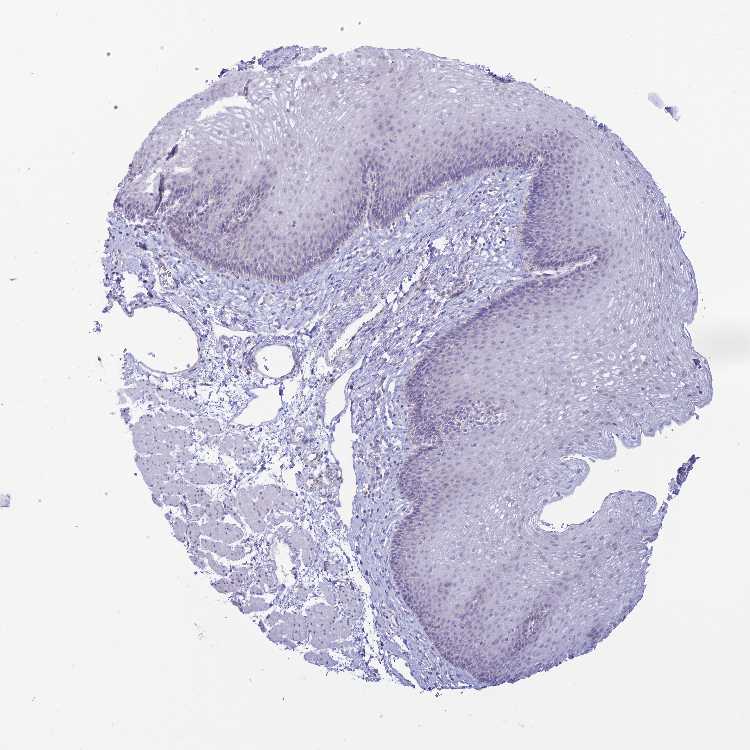

TISSUE PRIMARY DATA ESOPHAGUS Show tissue menu

Esophagus

ESOPHAGUS - Antibody stainingi

Antibody staining in the annotated cell types in the current human tissue is reported as not detected, low, medium, or high, based on conventional immunohistochemistry profiling in selected tissues. This score is based on the combination of the staining intensity and fraction of stained cells.

Each image is clickable and will lead to virtual microscopy that enables deeper exploration of all samples and also displays staining intensity scores, fraction scores and subcellular localization as well as patient and tissue information for each sample.

Antibody HPA042995Antibody HPA048454

Squamous epithelial cells Not detectedMedium